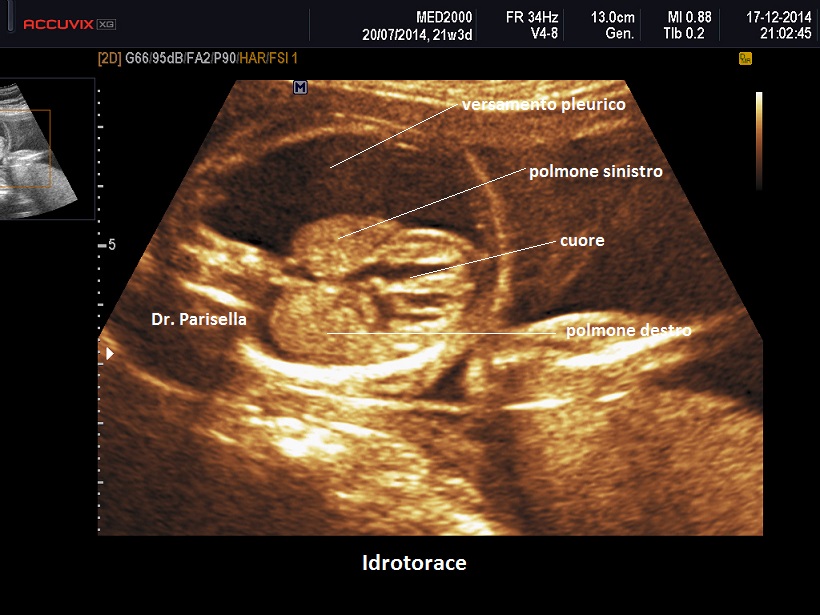

I segni ecografici sono:

• edema del sottocute: spessore > 5 mm.

• iperplacentosi: spessore placentare > 6 cm.

• polidramnios

• ascite

• effusione pericardica

• effusione pleurica

Come detto in precedenza l'accumulo di liquido deve interessare almeno due compartimenti.

Un primo orientamento sulle cause di idrope può essere fatto attraverso la localizzazione dell'accumulo di liquido: un accumulo generalizzato sin dal principio orienta verso una causa sistemica come l'anemia, mentre un accumulo inizialmente localizzato porta ad orientarsi verso una patologia locale ( es.: versamento pleurico >>>> Malformazione Adenomatoide Cistica Congenita del polmone).